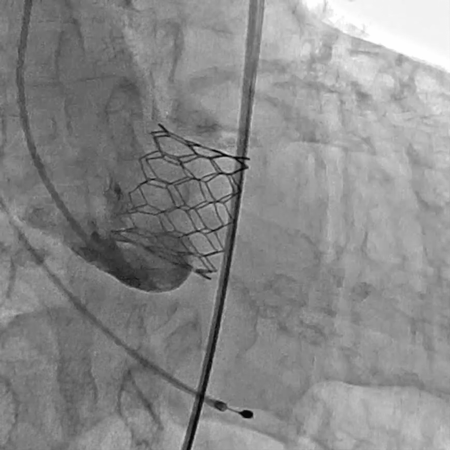

术前经详尽影像学重建、评估及病例讨论,计划经右侧股动脉植入25#球扩式介入瓣。术中使用21#球囊进行预扩,植入25# Renatus®介入主动脉瓣。手术全程顺利,血流动力学稳定,主动脉瓣植入位置理想,功能表现出色,DSA及TEE评估无瓣中反流,仅有轻微瓣周反流。主动脉瓣峰值流速由术前4.4m/s降至1.6m/s,平均压差由术前49mmHg降至4.4mmHg。

球扩释放瓣膜 术后主动脉根部造影